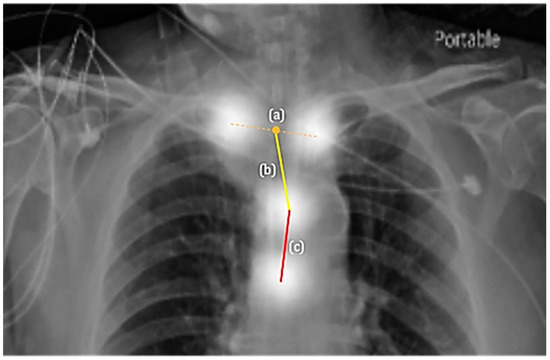

2.3.1. The First Component: Two-Stage Key Point Detection Model

2.3.2. The Second Component: Appropriateness Prediction

3.1. Key Point Detection